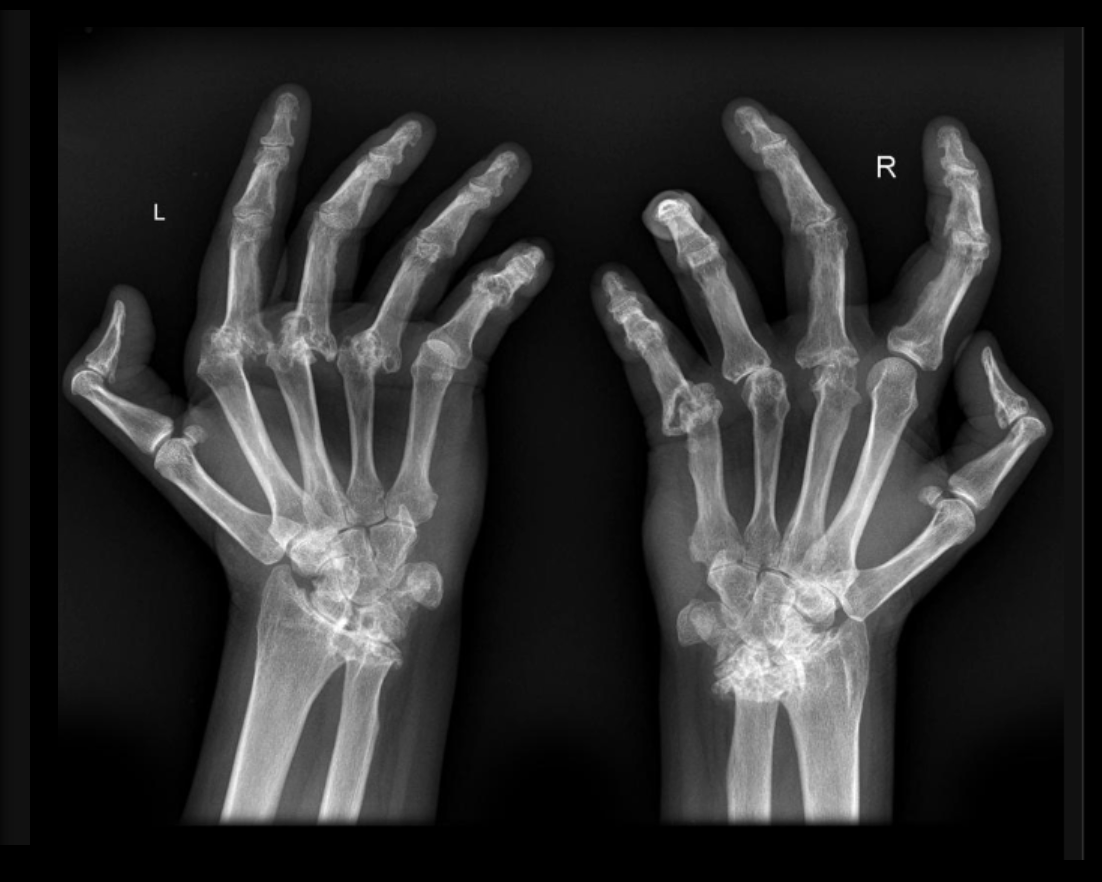

What pathological disease does this X-Ray show?

Rheumatoid Arthritis